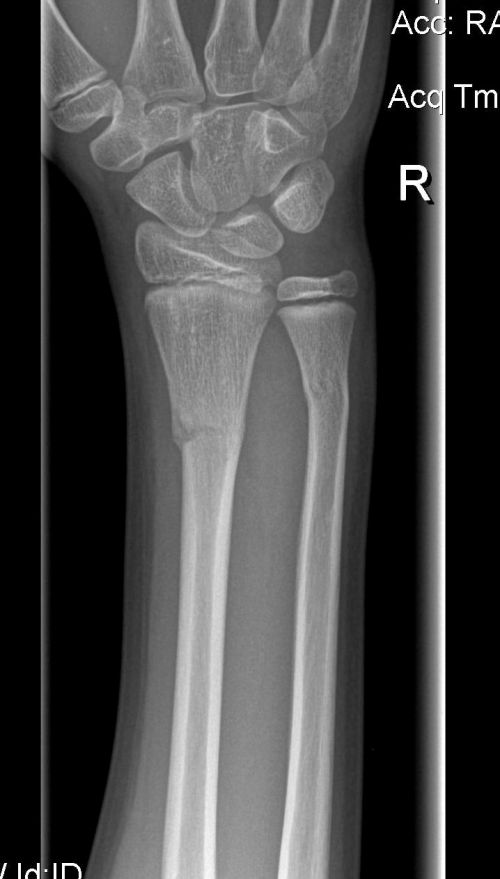

Nikhil broke his arm last week – both radius and ulna. He’ll be in a cast for the next 4 weeks. Fortunately, no surgery needed but the first few days are quite painful.

At the hospital, they now send you home with a CD of x-ray pictures. This is cool – no more films.